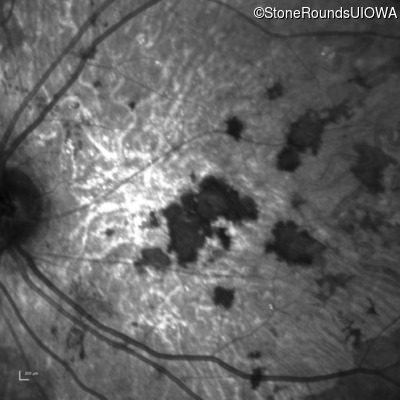

Blue Autofluorescence - Right - 20/150 sc

Exemplar